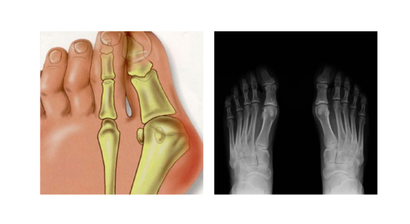

Fußchirurgie

ist eine der häufigsten Fehlbildungen der Zehen. Er entsteht meistens durch das dauerhafte Tragen zu enger oder unbequemer Schuhe. Deshalb leiden...